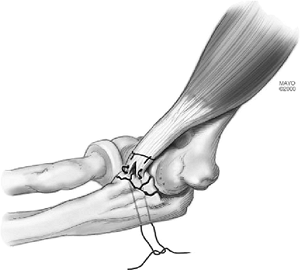

that a varus moment applied to the elbow in an extended position may

create a sagittal coronoid fracture. This fracture usually includes the

attachment of the ulnar collateral ligament on the sublime tubercle (Fig. 7-3) and might be termed a type IV or anterior medial fracture.

Figure 7-3.

A sagittal fracture occurs from varus axial load with or without comminution and usually involves attachment of the anterior medial collateral ligament. |